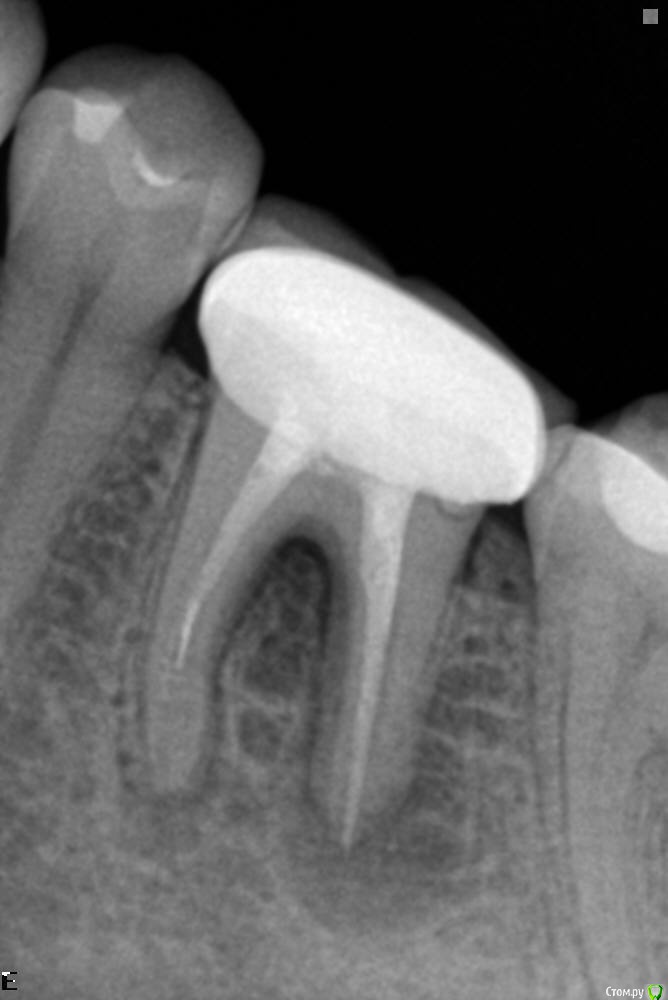

Jammy Опубликовано 5 августа, 2019 Поделиться Опубликовано 5 августа, 2019 Доброго времени суток. В январе зуб был протезирован (коронка) . Буквально несколько дней назад начал появляться свищ на десне.Сделала снимок,показала специалистам - терапевту стоматологу из местной поликлиники и врачу из частной клиники. Мнения разделились. Один говорит, что зуб нужно удалять и ставить имплант. Другой предложил лечение с чисткой каналов и последующим протезированием, но, говорит, что лечение может не помочь и зуб придётся удалять. И я теперь не знаю, что делать. Напишите, пожалуйста, Вашу точку зрения. Благодарю Ссылка на комментарий

St. Опубликовано 5 августа, 2019 Поделиться Опубликовано 5 августа, 2019 Добрый день. Никакой имплант не будет лучше своего зуба. Я бы пробовала сохранить перелечив каналы. Шанс на успех достаточно высокий, и только если не поможет рассматривала вариант удаления и имплантации Ссылка на комментарий